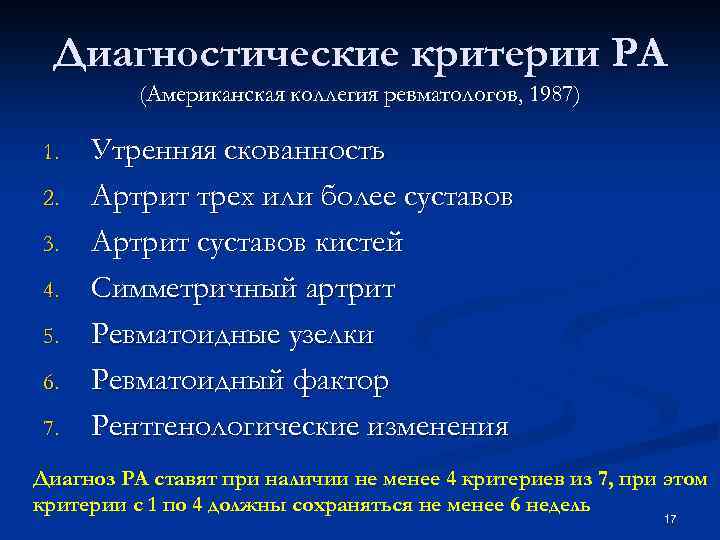

Диагностические критерии РА (Американская коллегия ревматологов, 1987) 1. 2. 3. 4. 5. 6. 7. Утренняя скованность Артрит трех или более суставов Артрит суставов кистей Симметричный артрит Ревматоидные узелки Ревматоидный фактор Рентгенологические изменения Диагноз РА ставят при наличии не менее 4 критериев из 7, при этом критерии с 1 по 4 должны сохраняться не менее 6 недель 17

Диагностические критерии РА (Американская коллегия ревматологов, 1987) 1. 2. 3. 4. 5. 6. 7. Утренняя скованность Артрит трех или более суставов Артрит суставов кистей Симметричный артрит Ревматоидные узелки Ревматоидный фактор Рентгенологические изменения Диагноз РА ставят при наличии не менее 4 критериев из 7, при этом критерии с 1 по 4 должны сохраняться не менее 6 недель 17